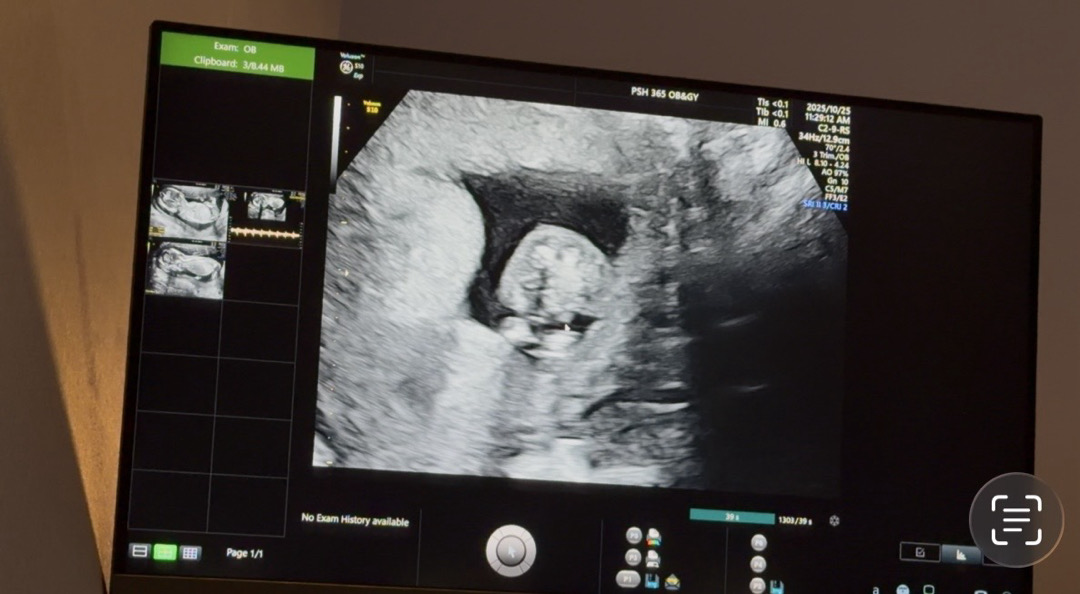

12주에 니프티검사하고 어제 딸이라고 연락받았는데 배가 아파 들러본 서브병원에서 고추같은게 보인다고 하셔서요 …! 7,80%정도는 남자로 보인다는데 뭐가 맞을까요 …? ㅠㅠ 화살표로 가르킨 부분이 고추 같다고 하셨어요

탯줄이지 않을까요?? 니프티 97퍼센트 정확하다고 하는데 3퍼센트에 해당될 수 있을수도..!